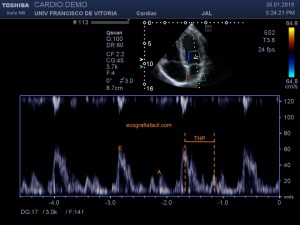

143. Ecocardiografía.Plano Apical 5 Cámaras.